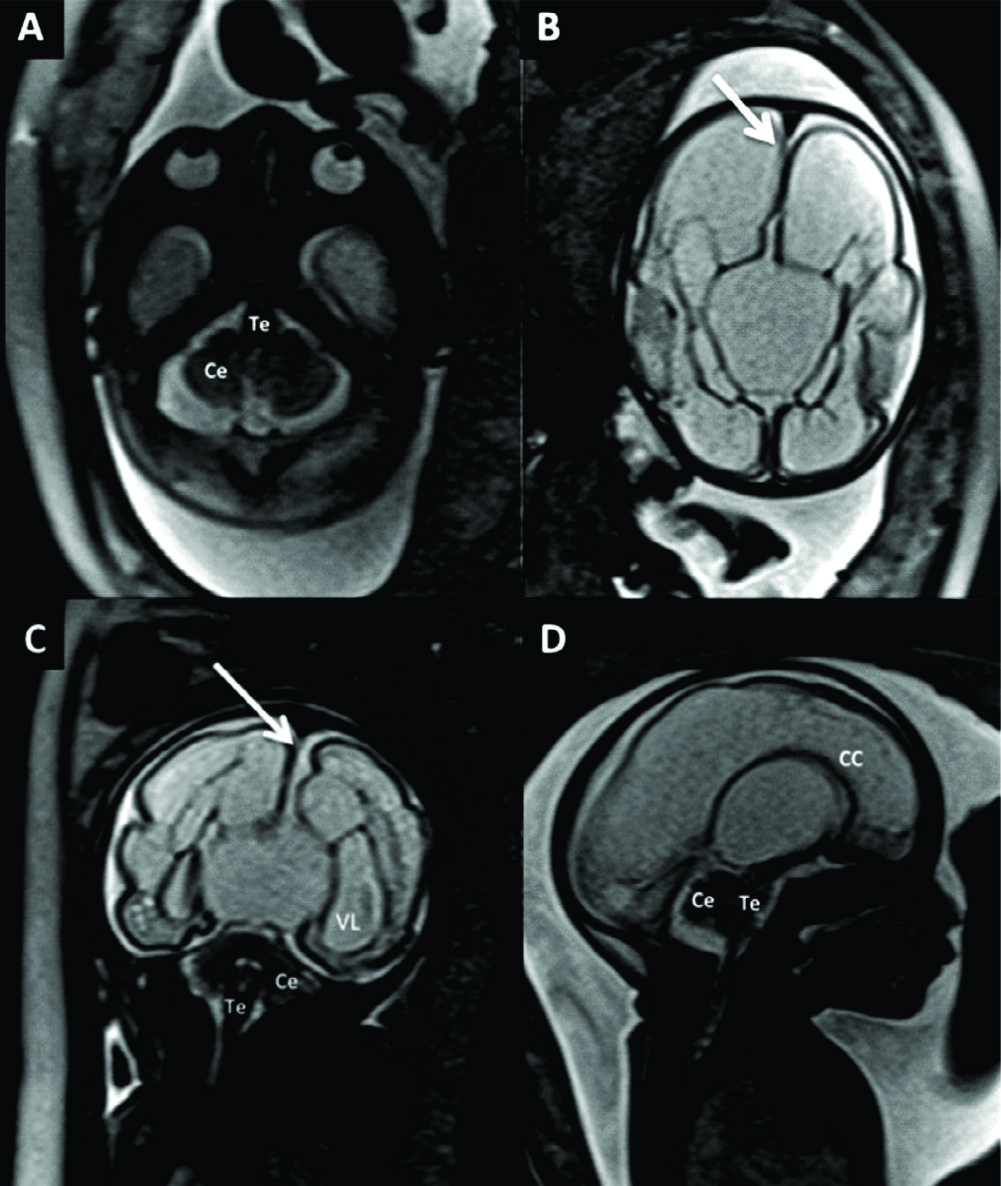

Figura 1

RM Fetal Normal (Edad Gestacional: 27 semanas).

Corte sagital en línea media (A) y corte axial a nivel bi-talámico (B) de cerebro fetal normal en la semana 27 (secuencia rápida T2). En la imagen de línea media se identifica claramente el cuerpo calloso (CC) y la cisura calcarina (è) así como también las estructuras de la fosa posterior con un desarrollo acorde.

En el plano axial se identifica la línea media y la región ganglio-basal con anatomía normal y un patrón gírico acorde a la edad gestacional con un esbozo de cisura silviana (CS).

Los diferentes sectores del sistema ventricular se identifican claramente: ventrículos laterales (VL), 3er ventrículo (situado entre ambos tálamos (T)) y IV ventrículo (situado entre el cerebelo (Ce) y tronco encefálico (Te)).